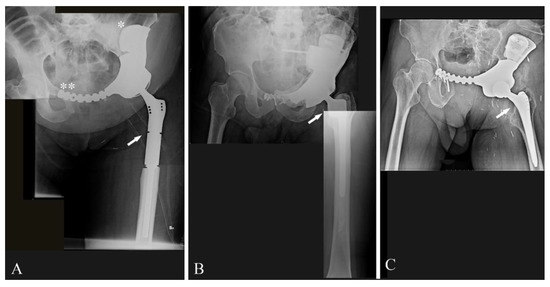

- The site: the aim of reconstruction after pelvic resection is to restore hip stability by giving the articulation a pivot. Acetabulum sparing is the keystone. Reconstruction can be performed with a hip prosthesis that includes a cup with an iliac stem when part of the anterior or posterior column is spared. When resection includes the acetabular roof (Figure 3A), an acetabulum with an iliac stem does not have sufficient bone support, so 3DPTCMP is a possible solution (Figure 3C right side); the 3DPTCMP should be linked to a spine stabilization to neutralize vertical cutting forces when resection includes the sacrum-iliac joint (Figure 5A,B).

- Prosthesis shape: most prostheses were constructed trying to reproduce normal bone anatomy (Figure 4A–C). Actually, this tactic could cause problems as wound dehiscence due to skin decubitus on the prosthesis; taking this into consideration, the option of designing a low-profile prosthesis has to be taken into account (Figure 5A,B): when the tumor involves the iliac wing, the prosthesis could simply connect the sacrum-iliac joint to the hip without reproducing the iliac wing’s shape (Figure 5A,B). Currently, several prosthesis designs are proposed in the literature.

- The fixation: several solutions are possible; the first prostheses had a voluminous plate as an extension, which was fixed with screws to another independent plate on the other side of the iliac wing (“wafer fixation”) (Figure 4C); this technique could cause necrosis of the bone included between the plates, so, at present, an iliac stem is preferred to obtain primary stability, decreasing the size of the wafer fixation. In the last cases of the present series, the prostheses were produced with one or two stems which were inserted press-fit in the residual wing, obtaining a good primary stability with a probable lower damage of the bone’s vascular supply and a better osteointegration (Figure 7A). Park et al. in 2019, using a finite element analysis, showed how the shape of the plates of fixation play an important role in stress distribution. Further studies are advocated to find the best solutions [24].

- Hip reconstruction: a prosthetic cup is cemented inside the prosthetic acetabulum. In the first cases, a constrained system was used to reduce the risk of femoral prosthesis dislocation (Figure 4A,B); later on, a dual mobility system was adopted. Indeed, constrained hip prostheses transfer traction stress forces caused by the weight of the inferior limb directly on the bone–prosthesis interface while the dual mobility system is a less rigid strategy which should guarantee a better cushioning and may be at lower risk of prosthesis failure (Figure 3E,F). Both strategies are probably effective in preventing femoral head dislocation.